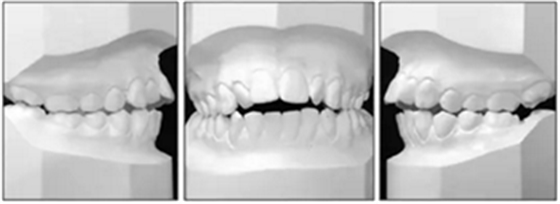

患者是一名12歲5個月的女孩,主訴是上頜牙列擁擠和前牙開合(圖1)。同時講話也受到了影響。無顳下頜關(guān)節(jié)癥狀。曾有過上頜擴(kuò)弓和前牙排齊的正畸治療史。

口外照顯示側(cè)貌凸,鼻唇角鈍,頦唇角銳和唇被動閉合。面部基本呈三等分。

口內(nèi)分析顯示呈II類1分類錯合畸形,前牙開合2mm和覆蓋3mm(圖2)。左側(cè)的后牙存在反合。上牙弓擁擠度2.5mm,下牙弓擁擠度1mm。中線一致。下頜前牙區(qū)牙齦稍有退縮。